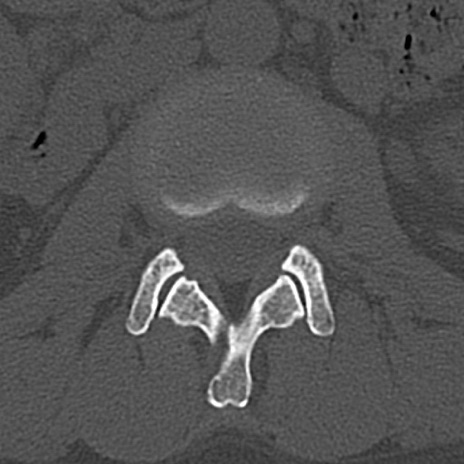

腰椎CT

横断像と矢状断像